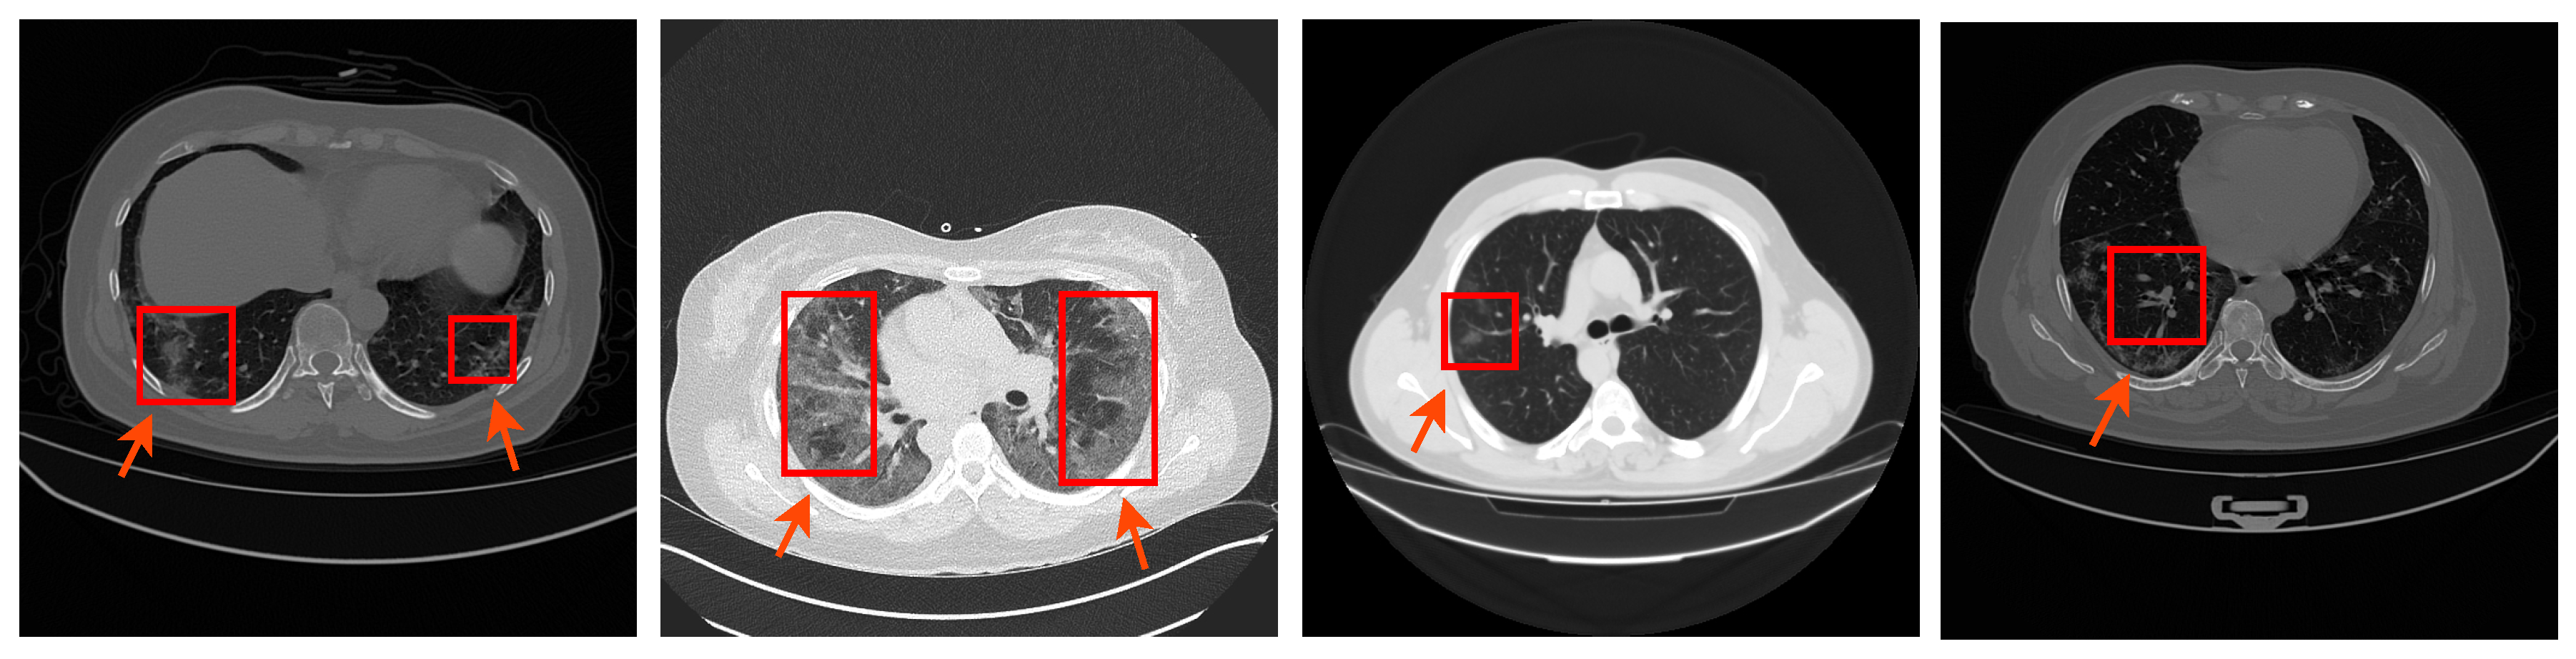

3.1.1. COVID-19 Lung CT Dataset